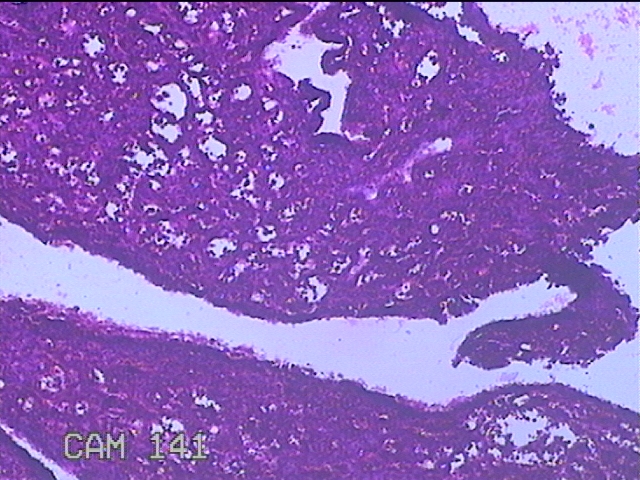

宫内容物

性别

女

年龄

16岁

临床诊断

1.不完全性药物流产 2.子宫内膜息肉?

一般病史

药流后阴道流血1月余。

标本名称

大体所见

灰白暗红色不规则碎组织3.5x2.8x0.7cm一堆,未发现明显的绒毛样组织。